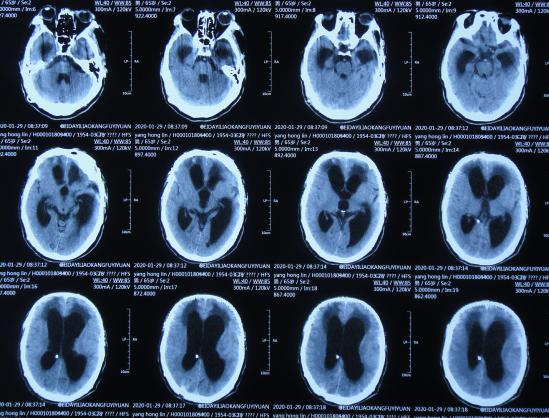

2020年3月18日(颅脑外伤开颅术后149天即颅骨修补术后95天即第2次脑室腹腔分流术后62天,先后经4家医院治疗后仍意识模糊,大小便*禁失**,脑积水,间断发热近2月)转住入李小勇脑脊液科。入院时:意识模糊,大小便*禁失**,体重较前明显减轻,体温高38度左右;头部可见引流管走向;右侧肢体活动差些;鼻饲流食( 图-30 );入院时头颅CT示颅骨修补术后、脑室引流术后仍脑积水,有水肿( 图-31 )。

图-30: 2020年3月18日入院时

图-31: 2020年3月18日头颅CT

入院次日拔除了原脑室腹腔分流管+脑室外引流术( 图-32 )。

图-32: 2020年3月19日头颅CT

入院治疗12天即2020年3月30日,查头颅CT示脑室有缩小、水肿有减轻( 图-33 )。

图-33: 2020年3月30日头颅CT

入院治疗19天即2020年4月6日,进行了脑室腹壁外引流术( 图-34 )。

图-34: 2020年4月6日头颅CT

入院治疗53天即2020年5月10日,复查头颅CT示脑室缩小( 图-38 )。

图-38: 2020年5月10日头颅CT

入院治疗71天即2020年5月28日,进行了脑室腹腔分流术。

入院治疗85天即2020年6月11日(脑外伤开颅术后经外院4家医院149天治后病情仍反复,但李小勇脑脊液科治85天康复出院);出院时:意识清楚,饮食变完全正常,体重较入院时明显增加,在俩人的搀扶下能缓慢的行走( 图-40 )。

图-40: 2020年6月11日出院时